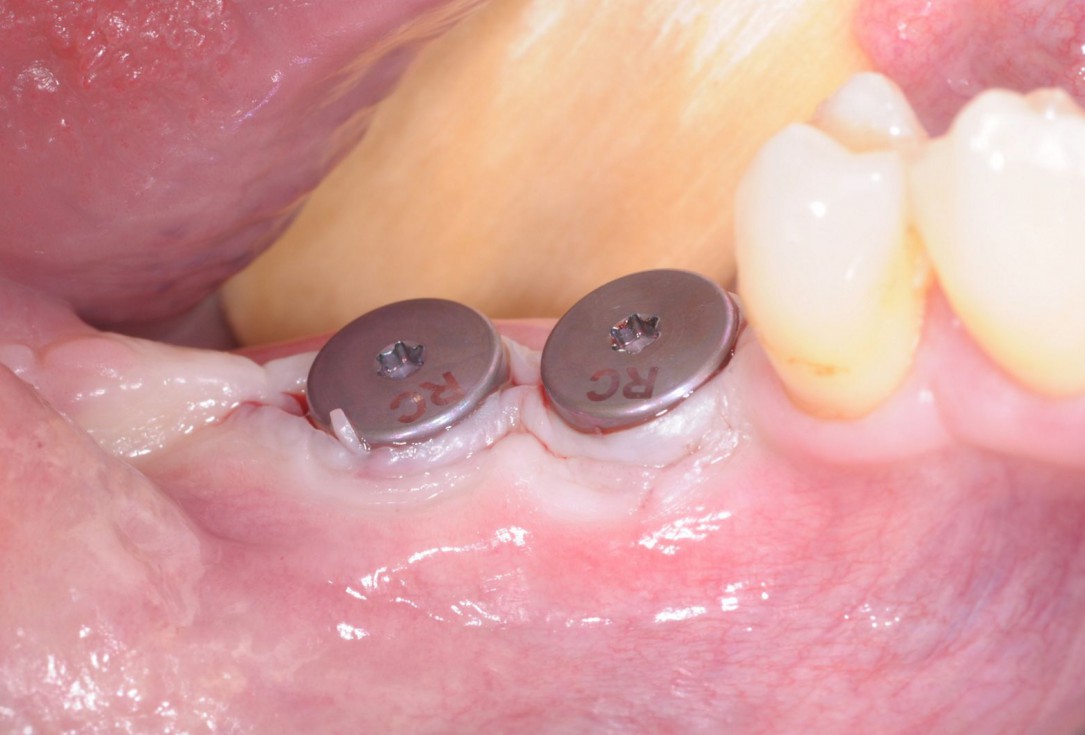

22/28 - Stab incision for reopening of the surgical site and installation of gingival formers - buccal viewThree-dimensional augmentation with maxgraft® cortico - Dr. R. Würdinger

23/28 - Stab incision for reopening of the surgical site and installation of gingival formers - occlusal viewThree-dimensional augmentation with maxgraft® cortico - Dr. R. Würdinger

24/28 - X-ray control scan after implant uncovering - excellent and stable osseous situationThree-dimensional augmentation with maxgraft® cortico - Dr. R. Würdinger